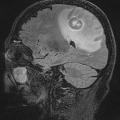

Lymphome cérébral

LYMPHOMES

LYMPHOME MALIN NON HODGKINIEN